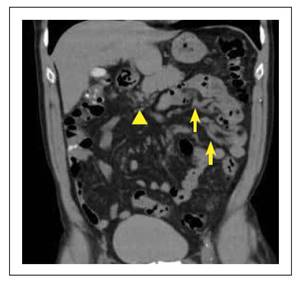

La entero TC reporta trombosis crónica de la VMS, con múltiples colaterales venosas adyacentes a la cabeza del páncreas, en el mesenterio superior y várices de distribución segmentaria a lo largo del yeyuno e íleon proximal (Figura 2).

Figura 2 Enterografía por tomografía (Entero TC). Colaterales venosas por trombosis de la VMS (∆). Várices ectópicas en yeyuno ( ).